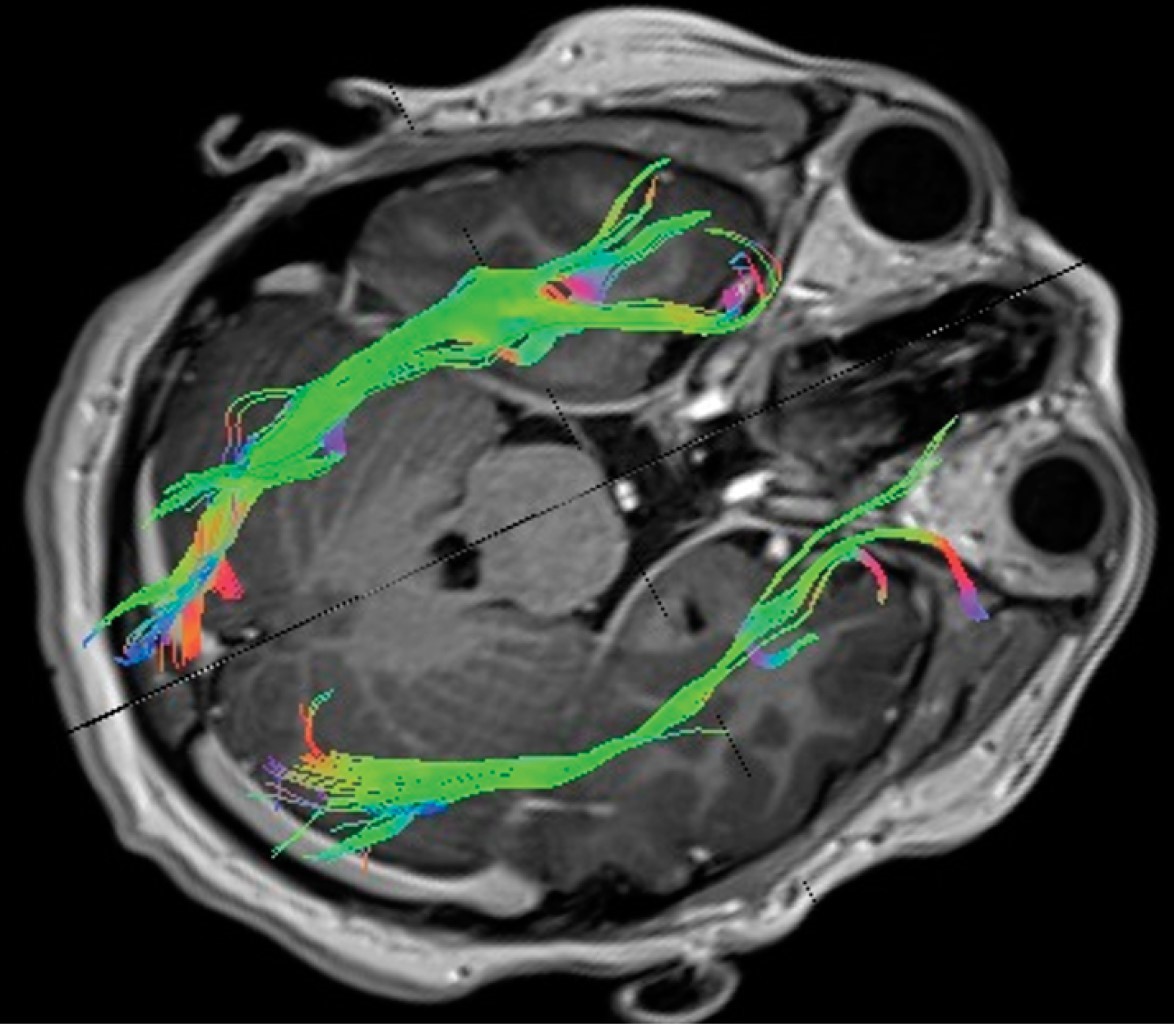

Paciente 2, 12 años, masculino, los valores de FA fueron de 0.000525248 (Figura 2) y de ADC 0.0200861.

Paciente 3, 15 años, masculino, los valores de FA fueron de 0.000104941 (Figura 3) y ADC 0.0198284.

La FA tiene un rango de 0 a 1, cuanto más cercano sea el valor numérico de este índice a 1, indicará que el tracto en estudio presenta preferencia por el movimiento o difusión en una dirección, secundario a la integridad de la capa de mielina que lo rodea (valor alto de FA), cuanto más cerca esté el valor de 0 (valor bajo de FA), reflejará una pérdida de la dirección preferencial, probablemente debido a una pérdida focal o difusa de la vaina de mielina.4 La fracción anisotrópica fue menor que los valores de control en nuestros tres pacientes, en el paciente 1 el resultado fue 0.000677609, en el paciente 2 fue 0.000525248, y en el paciente 3 fue 0.000104941, lo que refleja la presencia de desmielinización y daño axonal. Esto demuestra relación en cuanto a la base fisiopatológica de la enfermedad, donde la respuesta inmune provoca pérdida de mielina del nervio óptico y manifestaciones clínicas relacionadas con la neuritis óptica mediada o no por neuromielitis óptica o anticuerpos antiacuaporina, lo cual es interesante porque se inicia en la búsqueda definitiva, no sólo como cambios en las vías visuales sino también en un seguimiento a largo plazo, como un estudio que nos permita definir la severidad de la enfermedad y la respuesta a los tratamientos. En ese sentido el uso de la tractografía, especialmente en enfermedades neurológicas como la epilepsia y los tumores, ha abierto un camino más claro y novedoso en la evaluación de imágenes cerebrales, que ahora no sólo se limitan al conocimiento de las estructuras y su integridad, sino también al estudio de las vías y sus tractos.

En cuanto al ADC, éste nos habla de la difusión que existe entre las moléculas de agua con el tejido que la rodea a nivel extracelular. En nuestros tres pacientes los resultados obtenidos fueron inferiores en relación con el control (paciente 1: 0.00647864; paciente 2: 0.0200861; paciente 3: 0.0198284), estos hallazgos se observan cuando se produce un daño en el epineuro, dando como resultado un trastono en la difusibilidad, al entender que el epineuro es la capa nerviosa que puede sufrir un daño más inmediato ante procesos inflamatorios de diversas etiologías.4

En conclusión, los hallazgos en FA y ADC del nervio óptico podrían ser predictores del curso de la enfermedad; sin embargo, para establecer este hecho es necesaria una cohorte de pacientes con la enfermedad; por lo tanto, este estudio piloto abre la perspectiva. Es interesante observar en las imágenes por tractografía, como muestra nuestro estudio, que la desmielinización en pacientes con neuritis óptica no sólo se limita a la porción intraorbitaria del nervio, sino que también afecta a toda la vía óptica.